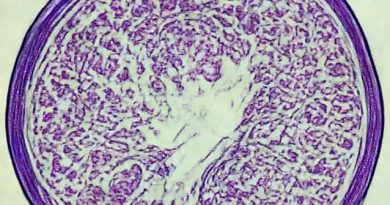

Low Grade Serous Carcinoma Pathology Outlines